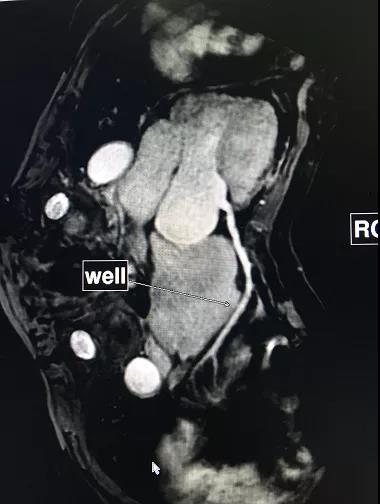

A:当然可以,一般胎儿我们建议孕期3个月以上孕妇检查,彩超在胎儿筛查中最常用,但是如果某些胎儿病变或者发育异常彩超无法明确时,磁共振就成了我们的不二选择;对于心脏的MRI检查技术已经相当成熟,我科有专业团队负责扫描与诊断,而且常常在CT上才能做的冠脉成像,在我们MRI上也可以完成,并且无需注射造影剂。

上图分别为成人、儿童(5岁)冠脉成像;